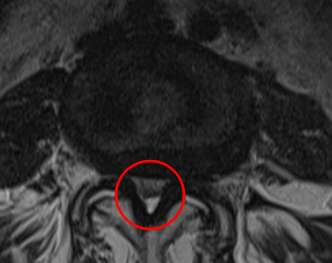

治療前

┃検査・診断

MRI画像を確認したところ、赤い枠で囲った箇所(L4/5)に脊柱管狭窄症の症状が認められ、かなり強く狭窄してしまっていました。腰痛や、左下肢の痛み、痺れの原因はこの狭窄だと判断しました。